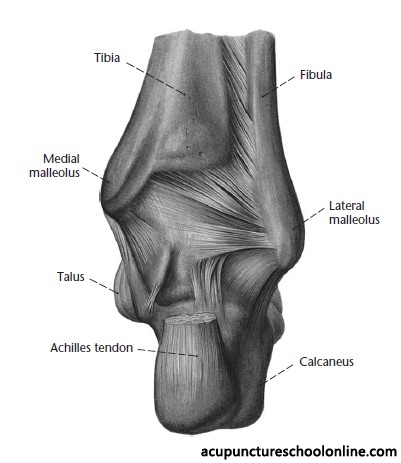

In the depression between the medial malleolus and the Achilles tendon, level with the prominence of the medial malleolus

Can be a target for disabling an opponent with a sword or knife by severing the Achilles tendon and possibly causing large amounts of bleeding from the posterior tibial artery. Its location makes it most likely to be struck on an already immobilised opponent and was most often used as a punishment on a captive.

Along with Shuiquan Kid-5 this is a possible location for the posterior tibial pulse. The ideal location is halfway between them at Pimenta's Point, the exact midpoint of a line drawn between the bony prominence of the medial malleolus and the insertion of the Achilles' tendon.

Basic information on location, needle depth, TCM actions, indications and combinations is taken from Deadman et al (2001): A Manual of Acupuncture with additional anatomical information researched by reference to Gray's Anatomy (38th Ed., 1995) unless otherwise referenced. Images were found on acupunctureschoolonline.com and can be traced back to Claudia Focks (2008) Atlas of Acupuncture originally. I cannot claim any credit or rights over them. Other sources should be quoted in the text.